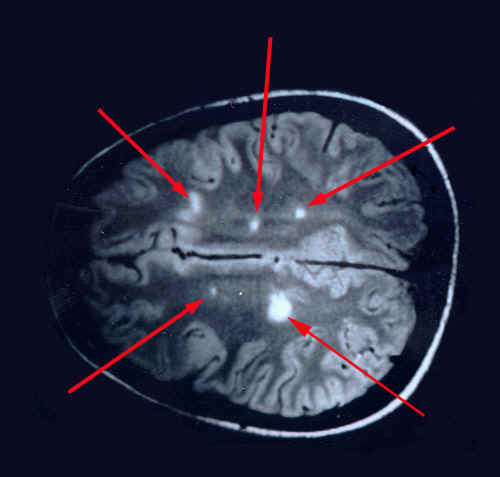

Un secondo particolare aspetto studiato al CRESM è l’effetto terapeutico della gravidanza sull’andamento della sclerosi multipla: è noto che durante la gravidanza la malattia è molto meno aggressiva. Studiando la modificazione dell’espressione dei geni durante la gravidanza, il CRESM ha individuato un gruppo di geni la cui espressione è alterata nelle donne con sclerosi multipla, ma normalizzato dalla gravidanza.

Questi geni sono un nuovo obiettivo terapeutico contro la malattia. Ricordiamo che la Sclerosi Multipla è al primo posto tra le cause di invalidità giovanile..